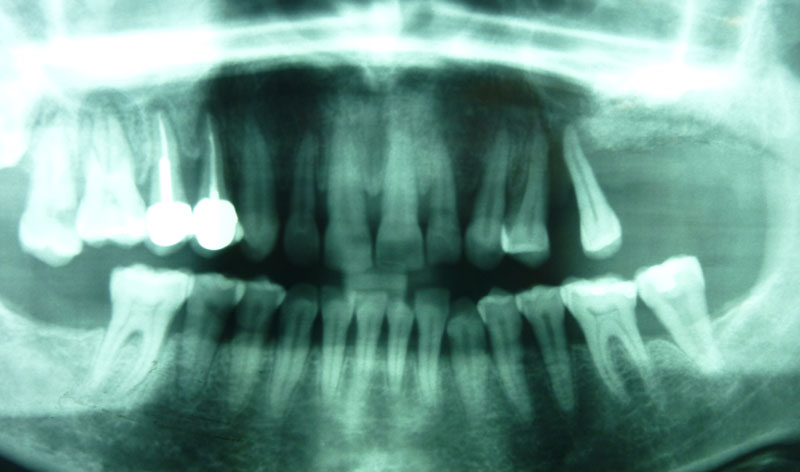

Se trata de una intervención que se efectúa bajo anestesia local. Está indicada en aquellos casos que requieren la colocación de implantes en el área posterior del maxilar superior donde el paciente no tiene el hueso suficiente para asegurar la fijación de los implantes.

Procedimiento: se realiza una incisión en la encía, se aborda el hueso maxilar superior realizando una pequeña apertura en el margen externo del maxilar, y se introduce un cemento formado por el propio hueso y sangre del paciente, y un material óseo conductor, que proporciona una serie de condiciones básicas para la formación de hueso.

Una vez realizada la intervención, en algunos casos se pueden colocar los implantes a la misma vez y en otros, es necesario esperar seis meses para que el material óseo forme un hueso con buena calidad que asegure el éxito de los implantes.